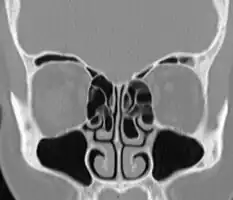

Bilateral concha bullosa, larger on the left -